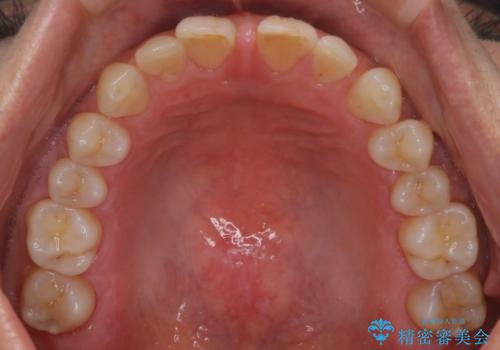

【審美装置】すきっ歯をワイヤー装置で治したい

- 前歯のすきっ歯が気になるということで来院されました。今回は抜歯はしないためワイヤー矯正かインビザライン矯正のどちらでも治療可能でしたが、患者さまのご希望により表のワイヤー装置にて治療をおこないました。

前歯に隙間がいくつかあったため、今回は上下でゴムかけを行いスペースを埋めるための力をかけて閉じました。もう少し早く終了する予定でしたが、ブラッシング不良による歯肉腫脹があり、一部スペースクローズに時間がかかりました。